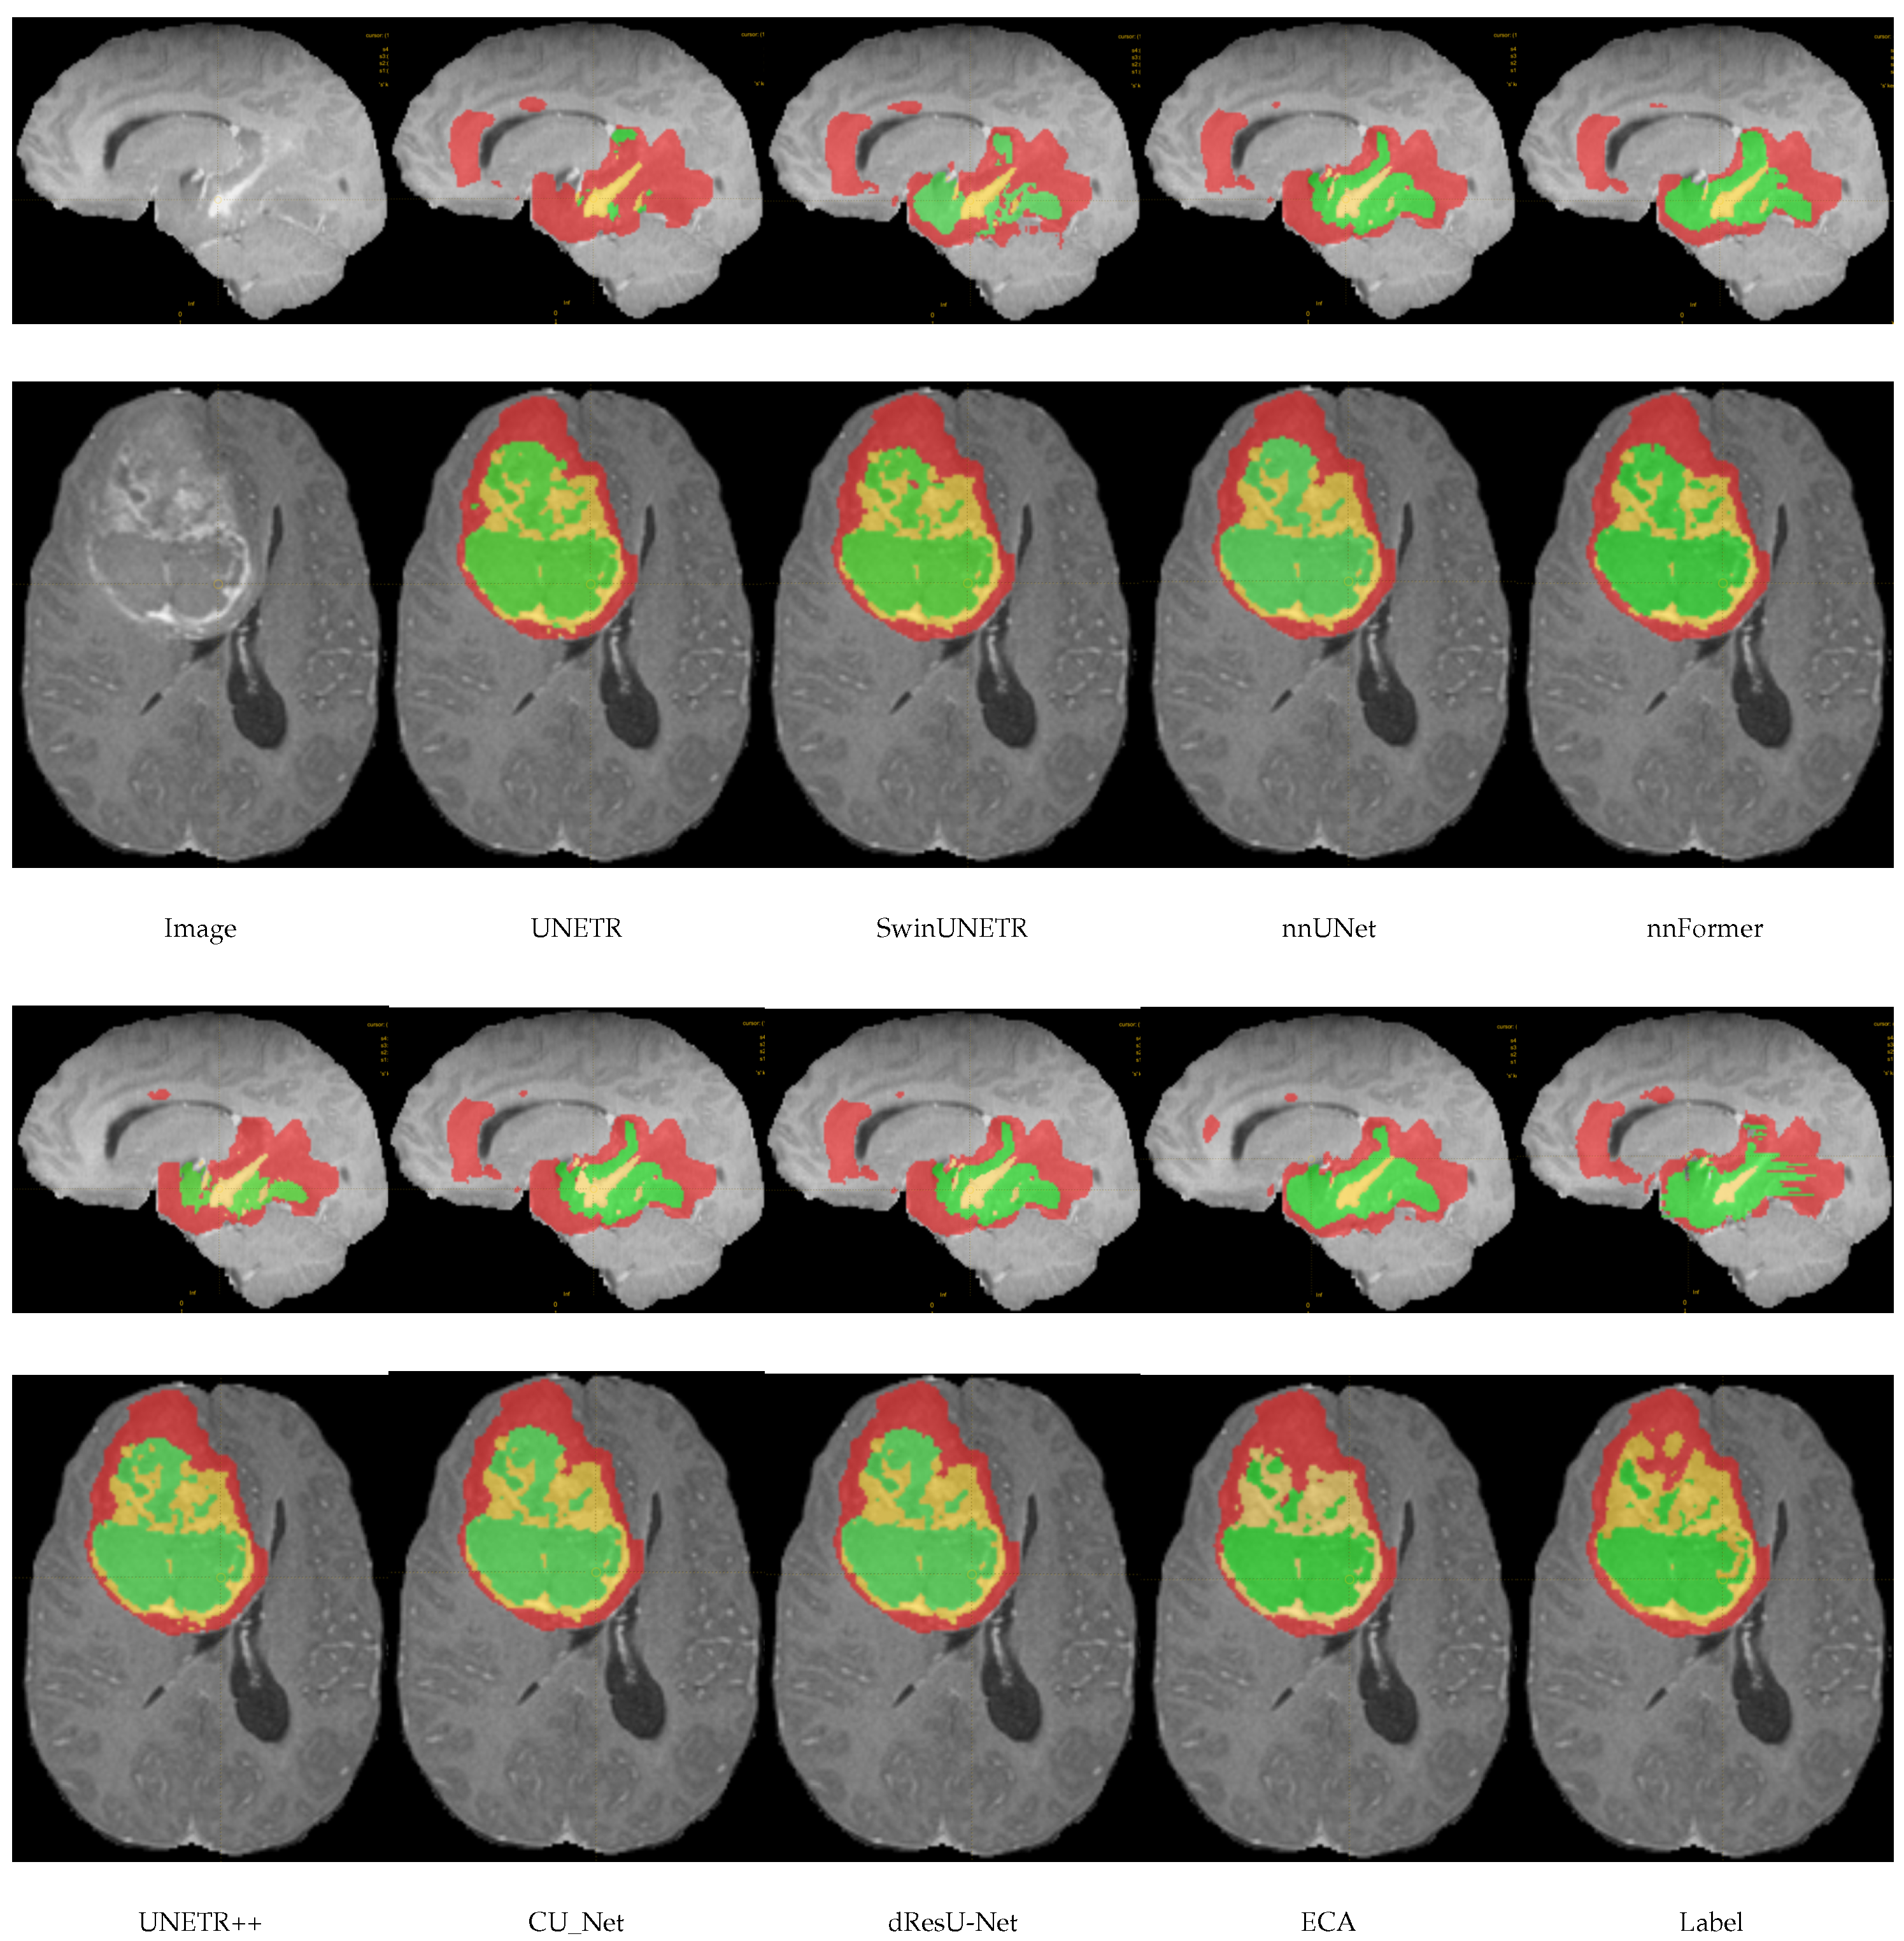

In this section, a comparison of the predictions of the ECA model with other models on the meningioma dataset is shown in Figure 4. By comparing the segmentation of each model, it can be seen that there are significant differences in the accuracy and boundary clarity of the different models in meningioma segmentation. UNETR’s predictions are unclear at the boundaries, and its segmentation areas are small, failing to segment the whole tumor. In addition, there is an obvious error in SwinUNETR, nnFormer, nnUNet, and UNETR++, that is, these models identify regions that are non-tumors as tumors. Compared with other models, the segmentation by ECA is the closest to the ground truth, especially in the meningioma regions with complex details, indicating that the feature extraction and boundary processing capabilities of ECA are superior.

Figure 4.

Visualization results of models on the meningioma dataset.

In this section, we show a comparison of the prediction results of the ECA model with other models on the BraTS2021 dataset, as shown in Figure 7. This figure shows the visual segmentation results of different models on the BraTS2021 dataset. Green, red, and yellow are used in the image to mark WT, TC, and ET, respectively. ECA showed high accuracy in the segmentations of all three regions. Compared with other models, the ECA model is able to capture the edges and shapes of the tumor more accurately, especially in the segmentation of the ET region. UNETR, SwinUNETR, and nnFormer may focus too much on capturing global information and the lack of local details, resulting in the accuracy in some regions, especially at the boundary between the TC and the ET, where the segmentation results of the model may not be sufficiently fine, with insufficient edge smoothing. dResU-Net and CU-Net are inadequate for edge extraction.

Figure 7.

Visual segmentation results of models on the BraTS2021 dataset.